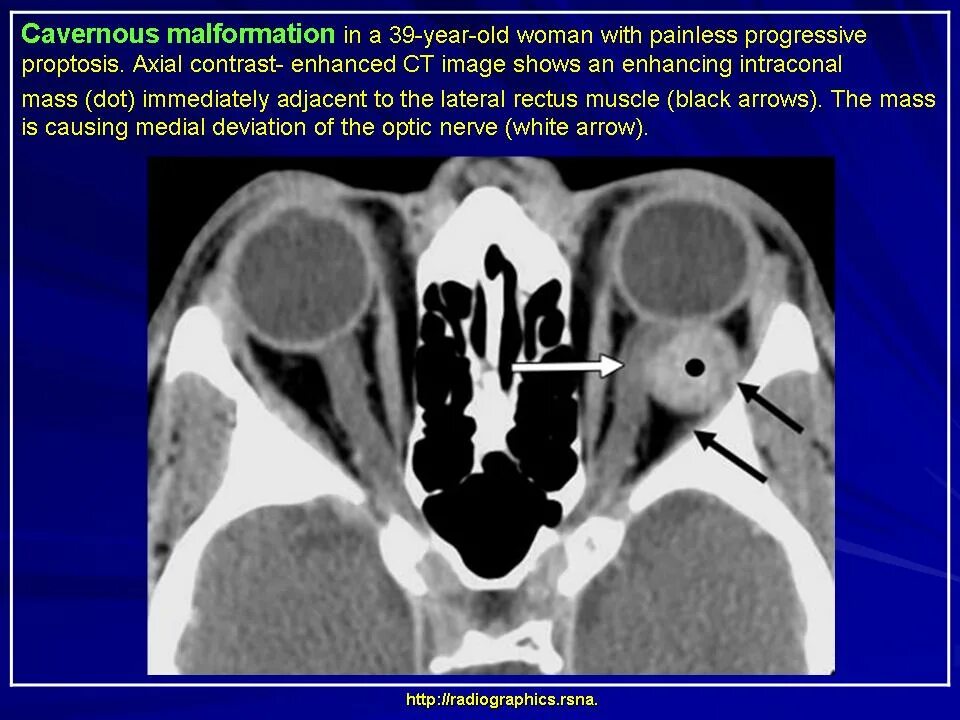

Данные кт